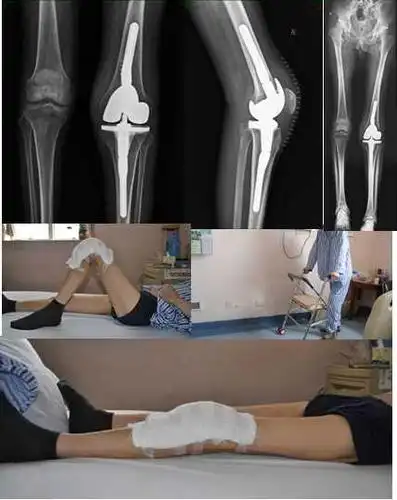

术后膝关节可伸直,外观及活动度满意,已经下床功能锻炼.